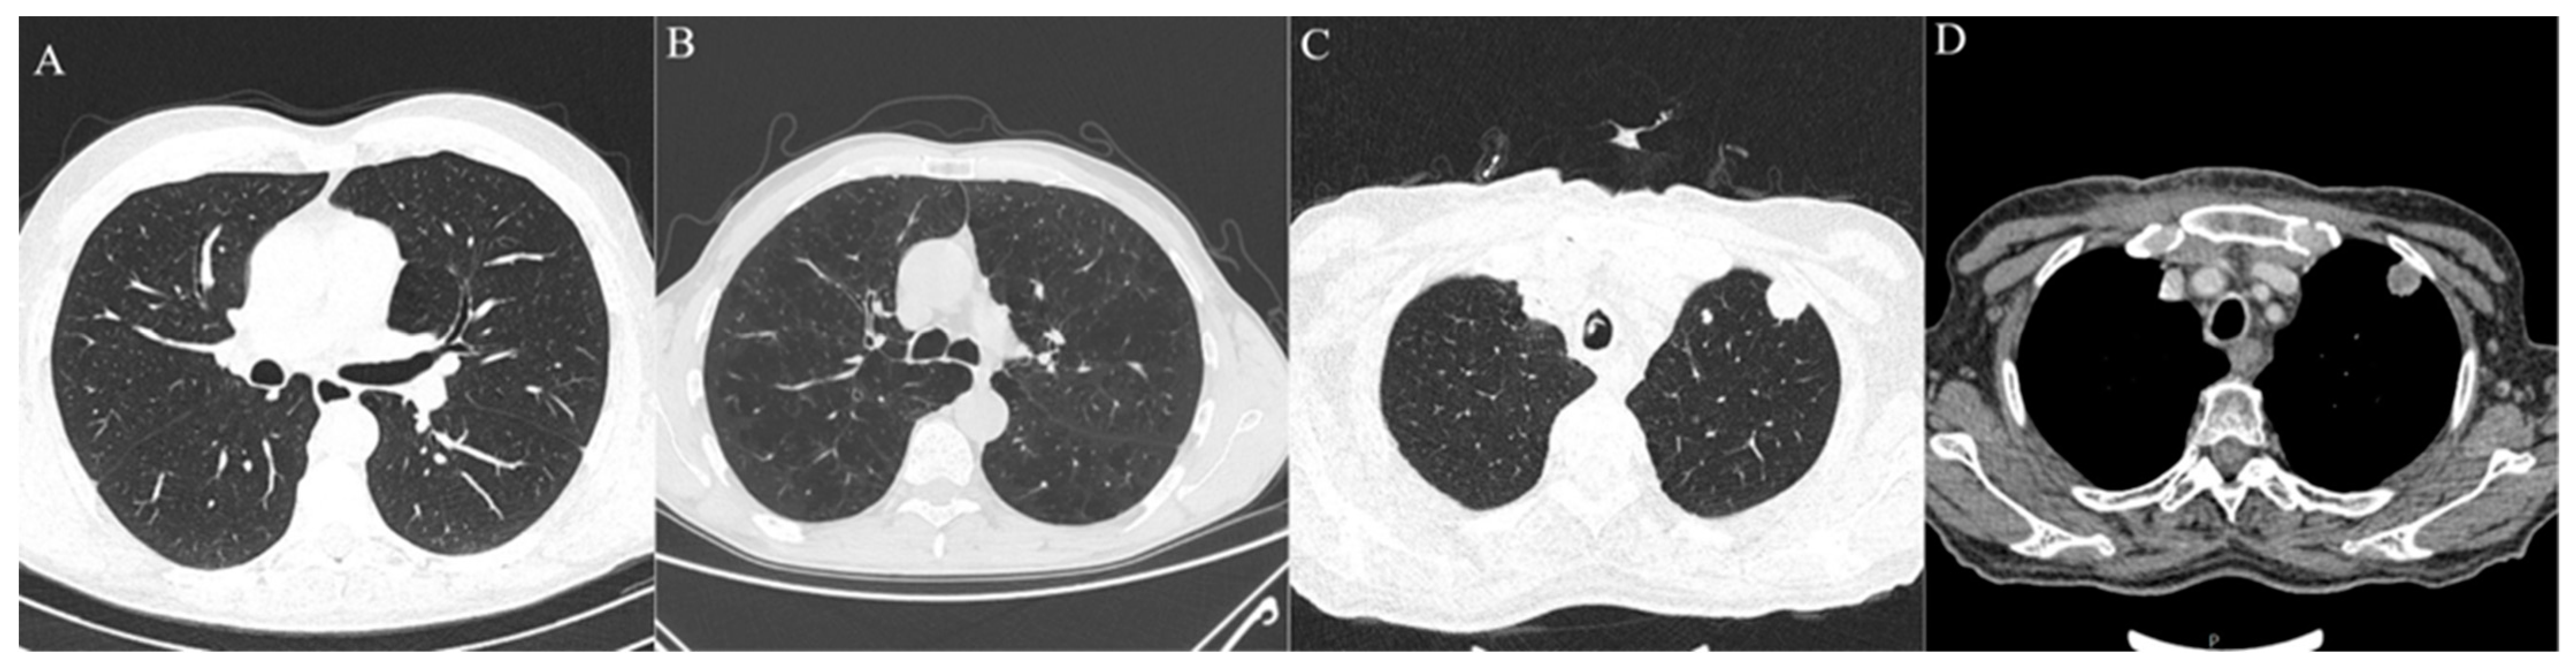

Figure 2.

Axial MSCT scans of pretreatment lung parenchyma demonstrating other radiological findings found in HNSCC patients. (A) Healthy lung parenchyma in lung window reconstruction. (B) Advanced centrilobular emphysema affecting all lung lobes seen as hyperlucent lung parenchyma, typical finding for heavy smokers in lung window reconstruction. (C,D) Same patient with lung metastasis which presents as soft tissue density, well circumscribed, round lesion with significant contrast enhancement and central necrosis in lung window reconstruction (C) and soft tissue window with intravenous contrast (D).